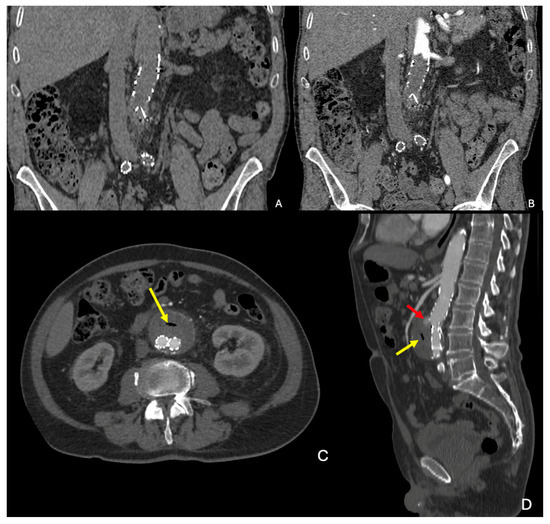

3. CTA Findings of Aneurysm Rupture

- Rakita, D.; Newatia, A.; Hines, J.J.; Siegel, D.N.; Friedman, B. Spectrum of CT Findings in Rupture and Impending Rupture of Abdominal Aortic Aneurysms. RadioGraphics 2007, 27, 497–507. [Google Scholar] [CrossRef]

- Schwartz, S.A.; Taljanovic, M.S.; Smyth, S.; O’Brien, M.J.; Rogers, L.F. CT Findings of Rupture, Impending Rupture, and Contained Rupture of Abdominal Aortic Aneurysms. Am. J. Roentgenol. 2007, 188, W57–W62. [Google Scholar] [CrossRef]